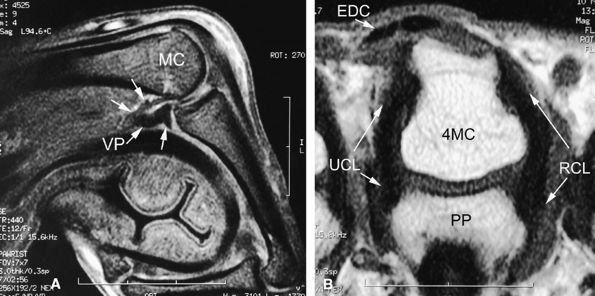

FIGURE 11.12 ● Stress MR examination with flexion of the metacarpophalangeal joint. (A) Sagittal fat-suppressed T1-weighted and (B) axial fast spin-echo T2-weighted images show the taut radial and ulnar collateral ligaments (RCL and UCL), which are seen along their course with a low signal. The stability of the extensor digitorum communis (EDC) tendon can also be assessed on these images. The volar plate (VP) is lax. MC, metacarpal; PP, proximal phalanx.

|